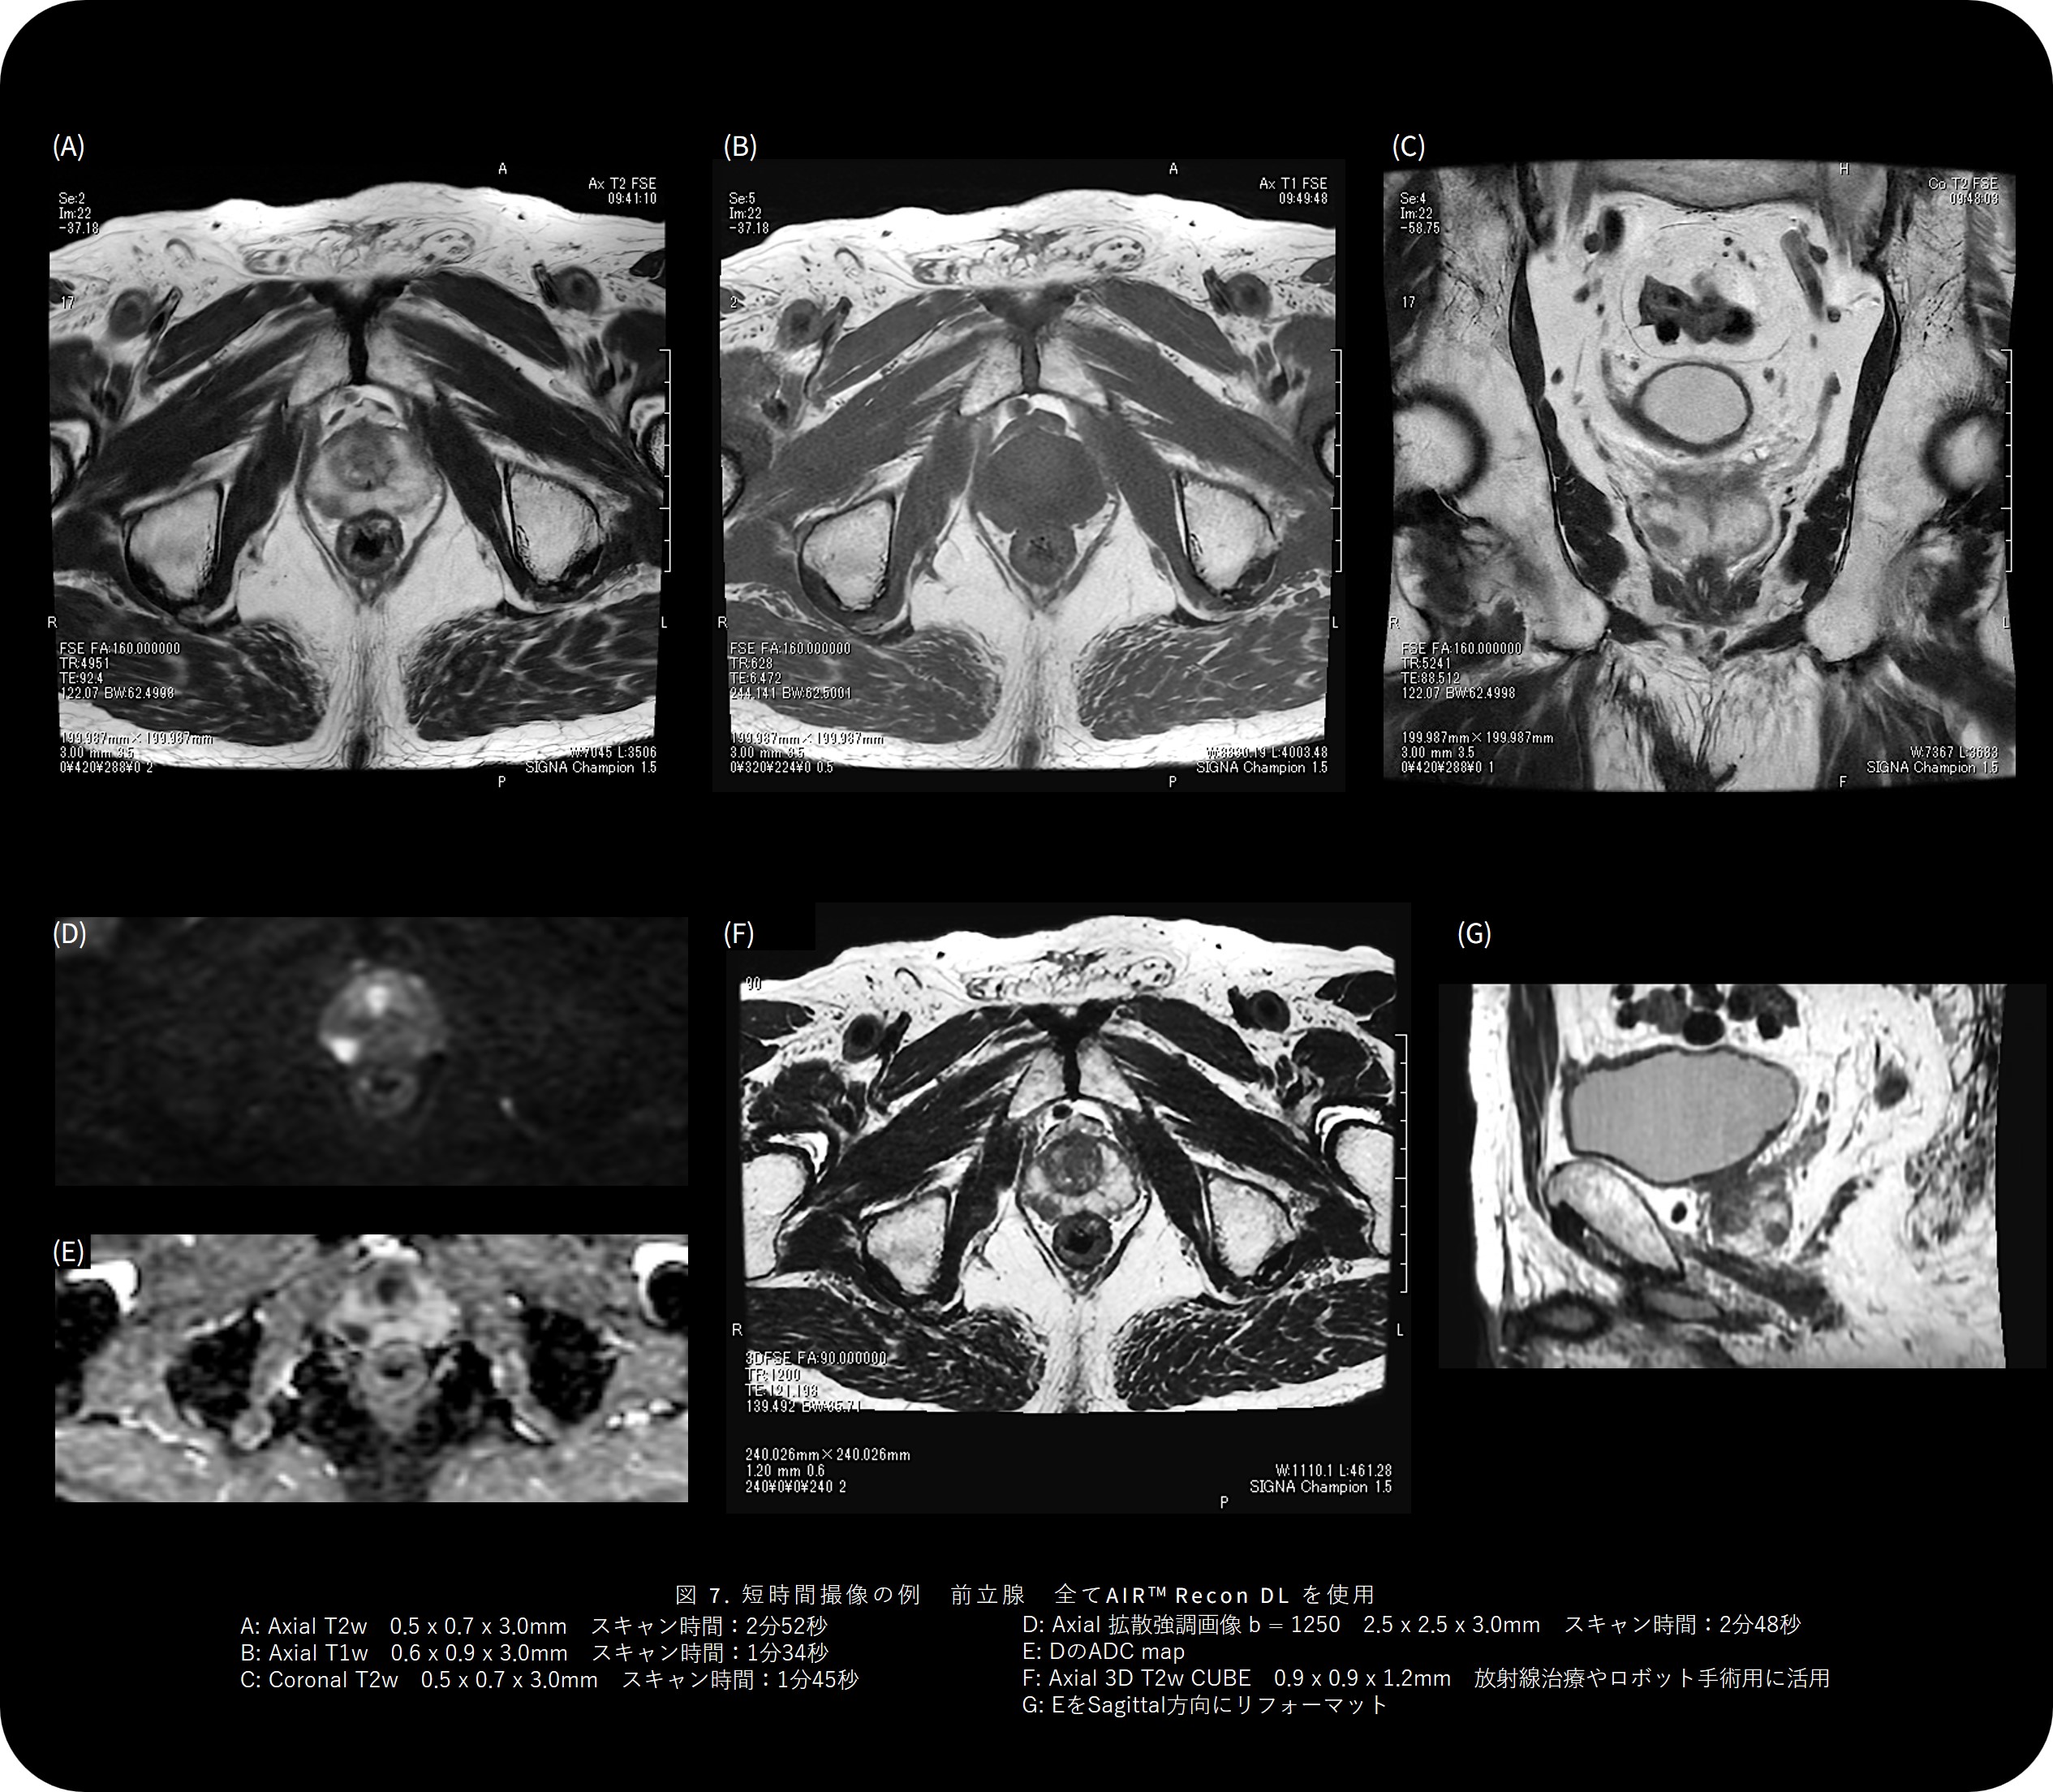

STIR画像は短時間撮像にもかかわらず、従来のサチュレーションありの画像よりもむしろコントラストが良好で、診断価値の高い画像が得られています。 (図4)

たとえば、脊椎全体の撮像時間は約11分。Fast scan では最短4分55秒で完了します。3D T2 Sagittal 画像もわずか2分48秒で取得でき、術前シミュレーションやナビゲーション用途でも十分な空間分解能を保っています。MPRで任意断面を自由に再構成できるため、脊椎変性疾患や圧迫骨折などの診断で医師から「CTと同等の情報量が得られる」との評価もいただいています。高齢の患者さんが多い当院では、検査中の体動や痛みを最小限にすることが重要であり、短時間で確実に撮像できることは、技師にとっても大きな安心につながっています。また、従来は動きによるアーチファクトで再撮像となるケースもありましたが、AIR™ Recon DLを用いることで1分半以内にノイズを抑えた画像を取得でき、再撮率が明らかに減少しました。

SIGNAChampion_Shinetsu05.jpg